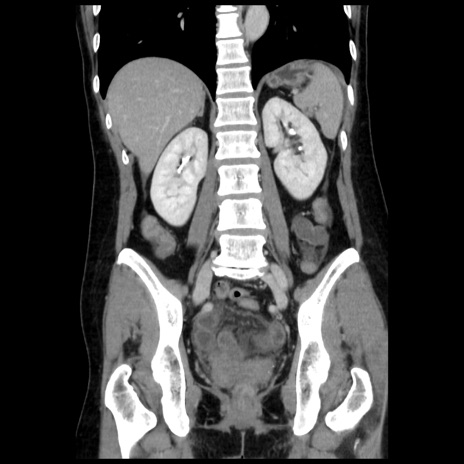

症例10(冠状断像)

【症例】 50歳代女性

【主訴】 腹痛

【現病歴】前日生レバーを食べた。今朝に排便あり。 昼前に突然発症の腹痛を生じ、当院救急外来を受診した。

【既往歴】 子宮筋腫にてで子宮全摘後

【身体所見】 意識清明、腹部:平坦、軟、下腹部やや左を中心に圧痛・反跳痛あり、筋性防御あり

【データ】WBC 7800、CRP 0.07